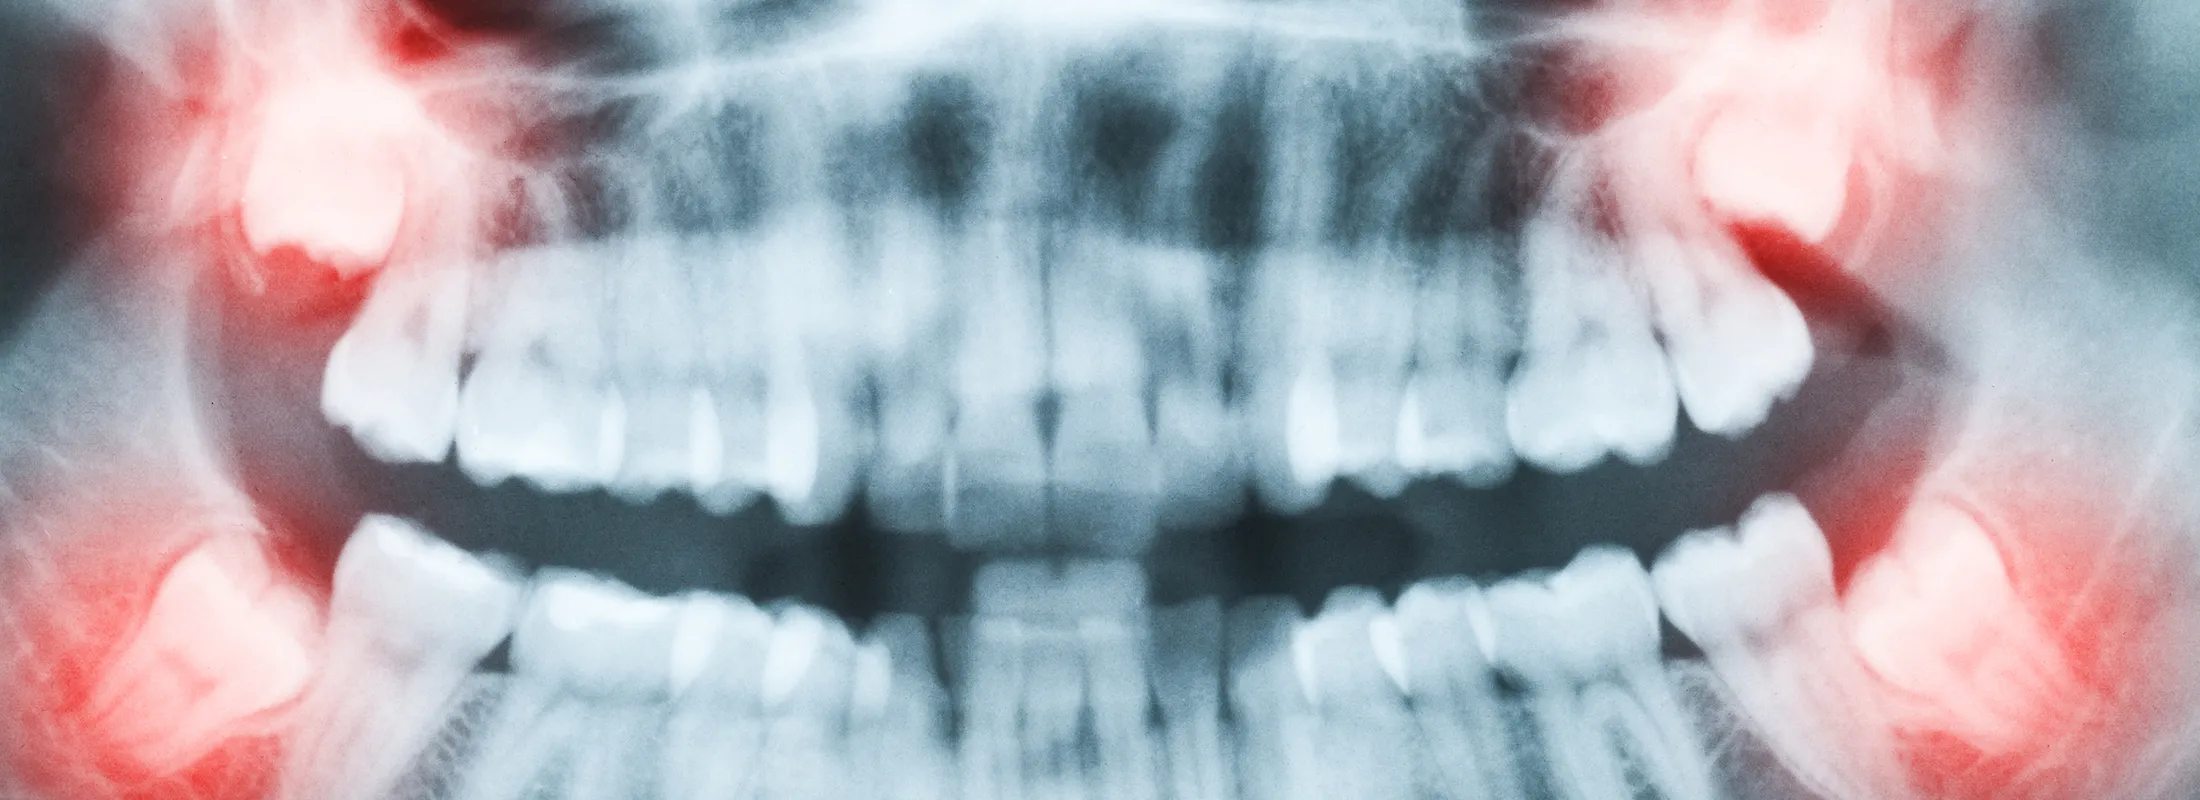

当院では、難症例も含むさまざまな親知らずの抜歯にも対応しています。親知らずが気になる方は、いつでもご相談ください

永久歯が生え揃った後、前歯の真ん中から数えて8番目に生えてくる歯を親知らず(智歯)と呼びます。現代では退化傾向にあり、生えてこないケースも少なくありません。親知らずが斜めに生えていたり、歯茎の内部で隣接する歯を圧迫している場合など、親知らずを残すリスクの方が高いと判断されるケースでは抜歯をする必要があります。

当院では、難症例も含むさまざまな親知らずの抜歯にも対応しています。症状に応じてCTを用いた的確な診断を行い、また痛みや腫れがご心配な方のために痛み止めや腫れ止めのお薬もご用意しております。